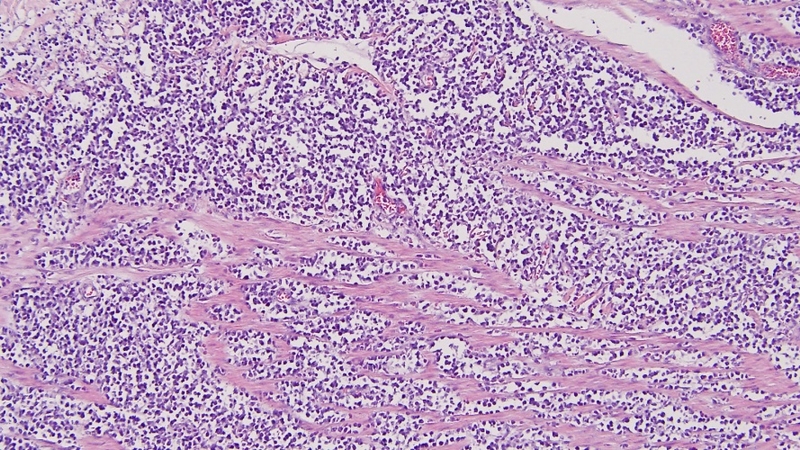

U lympho ruột non là một loại ung thư hiếm gặp bắt nguồn từ các tế bào lympho - một phần quan trọng của hệ thống miễn dịch trong cơ thể. Các tế bào này thường có nhiệm vụ bảo vệ cơ thể khỏi các yếu tố gây bệnh, tuy nhiên khi chúng phát triển bất thường và không kiểm soát được, chúng có thể tạo thành khối u trong ruột non. U lympho ruột non có thể ảnh hưởng nghiêm trọng đến chức năng tiêu hóa và sức khỏe tổng thể của người bệnh.

U lympho ruột non không phải là loại ung thư phổ biến nhất, nhưng vẫn chiếm một tỷ lệ đáng kể trong số các ung thư liên quan đến hệ tiêu hóa. Theo một đánh giá vào năm 2021, u lympho ruột non chiếm từ 20% đến 30% tổng số các trường hợp ung thư hạch đường tiêu hóa và chiếm 15% đến 20% trong tất cả các loại ung thư xuất hiện ở ruột non. Hai loại u lympho ruột non phổ biến nhất là u lympho tế bào B lớn lan tỏa (DLBCL) và u lympho MALT. DLBCL là loại ung thư hạch phát triển nhanh và phổ biến nhất, trong khi u lympho MALT lại phát triển chậm, thường ảnh hưởng đến mô lympho nằm trong niêm mạc đường tiêu hóa.